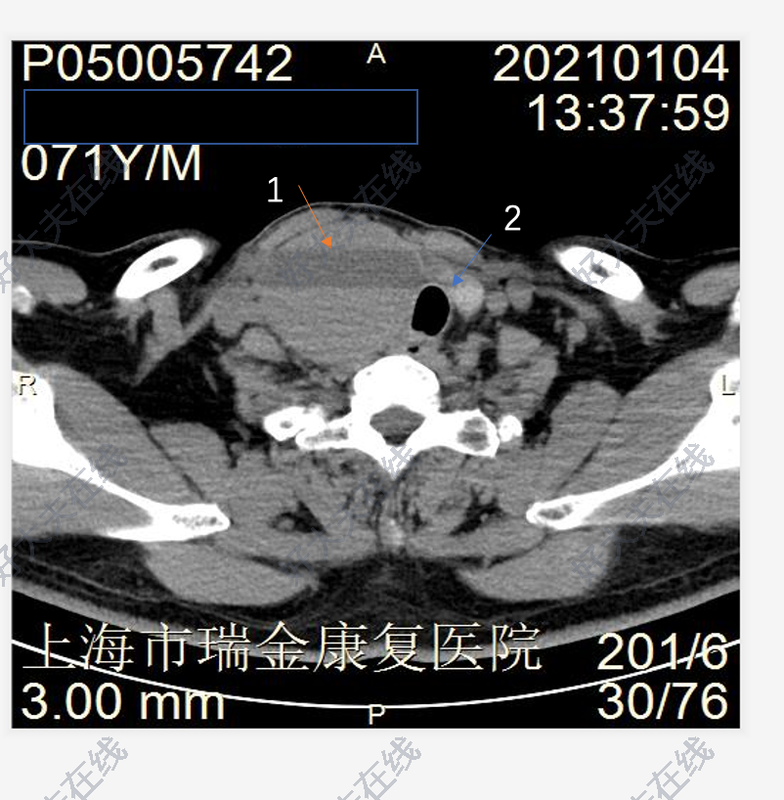

對(duì)于甲狀腺腫物,一般比較大的,采用手術(shù)切除。目前手術(shù)切除的技術(shù)以小切口微創(chuàng)手術(shù)為主,傳統(tǒng)的大切口甲狀腺手術(shù)由于不美觀做的越來越少了。最近有一個(gè)甲狀腺較大腫物的患者,找耳鼻喉鄭立崗醫(yī)生做了小切口甲狀腺腫物切除的手術(shù)?;颊哧悾?,42歲,廣東佛山人。患者1周前刷牙時(shí)無意中發(fā)現(xiàn)左側(cè)頸部腫物,腫物逐漸增大,偶伴有脹痛感,遂到我院門診查頸部CT示甲狀腺左側(cè)葉下極腫塊。為進(jìn)一步診治,門診擬頸部外表面腫物收住我科。患者術(shù)前檢查腫物直徑約3cm,比較大。這次做了一個(gè)4cm的小切口,逐層的暴露甲狀腺及腫物后切除腫物,術(shù)中注意保護(hù)喉返神經(jīng),完整切除腫物后縫合切口。整個(gè)的手術(shù)用時(shí)約1小時(shí),非常的順利。術(shù)后查房患者無明顯的不適,無手術(shù)相關(guān)的并發(fā)癥。對(duì)于甲狀腺腫物,小切口微創(chuàng)手術(shù)相對(duì)比較簡(jiǎn)單,并發(fā)癥少。是一個(gè)比較好的選擇。如果您還有什么問題,歡迎留言和耳鼻喉鄭立崗醫(yī)生進(jìn)一步交流。